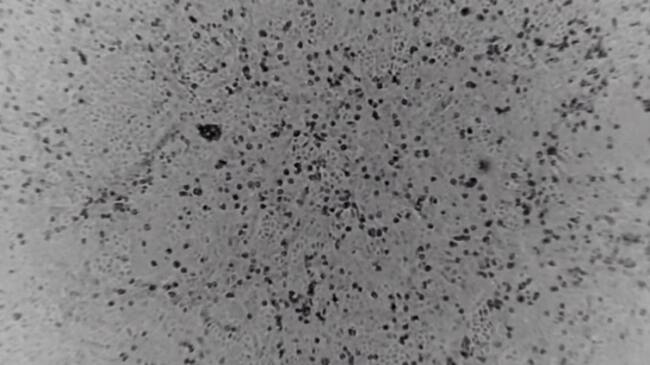

Coronavirus de Wuhan en cultivo / Julian Druce, The Doherty Institute.